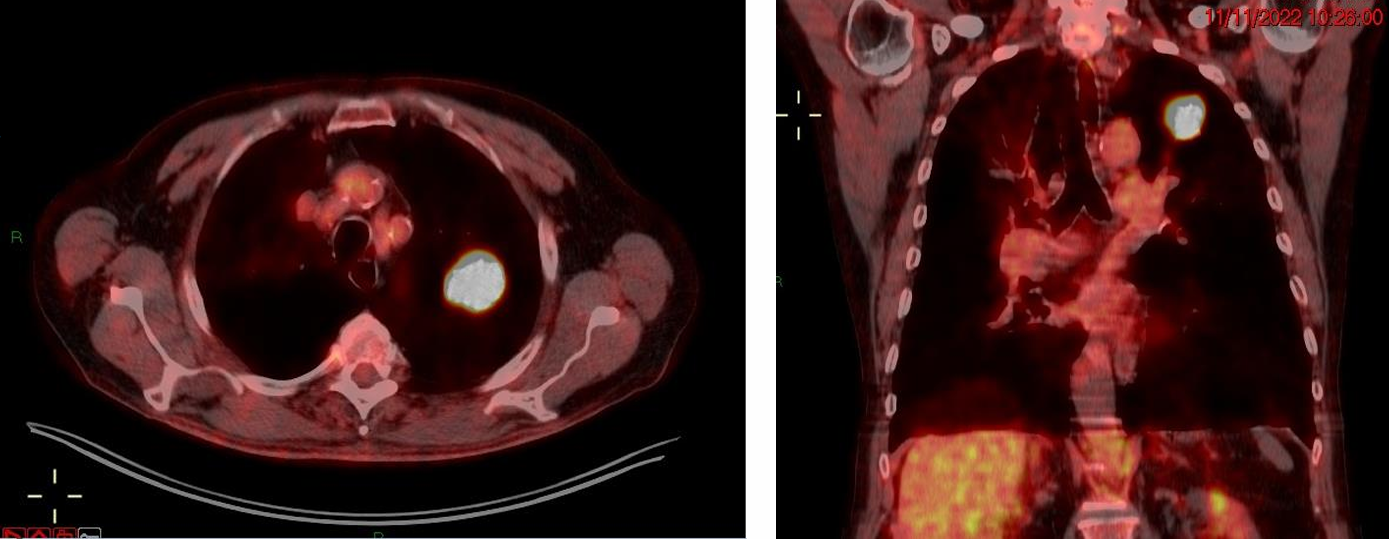

胸部CT(2022年11月):左上肺尖段可见一25mm的病灶,边缘呈毛刺状。双肺可见弥漫性混合型肺气肿,右上叶尖段有一巨大肺大疱(约10.7cm)。未见明确肿大的肺门及纵隔淋巴结,未见远处转移。

FDG-PET/CT(2022年11月11日):左上肺病灶显示高代谢活性,SUVmax高达19.8。